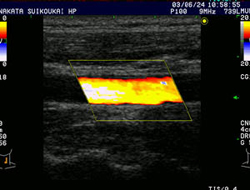

頚動脈エコー例

頚動脈エコー

(黄色にみえる部分は血流を示している)

頚動脈狭窄症例の動画をみる

[mpgファイル 776KB]